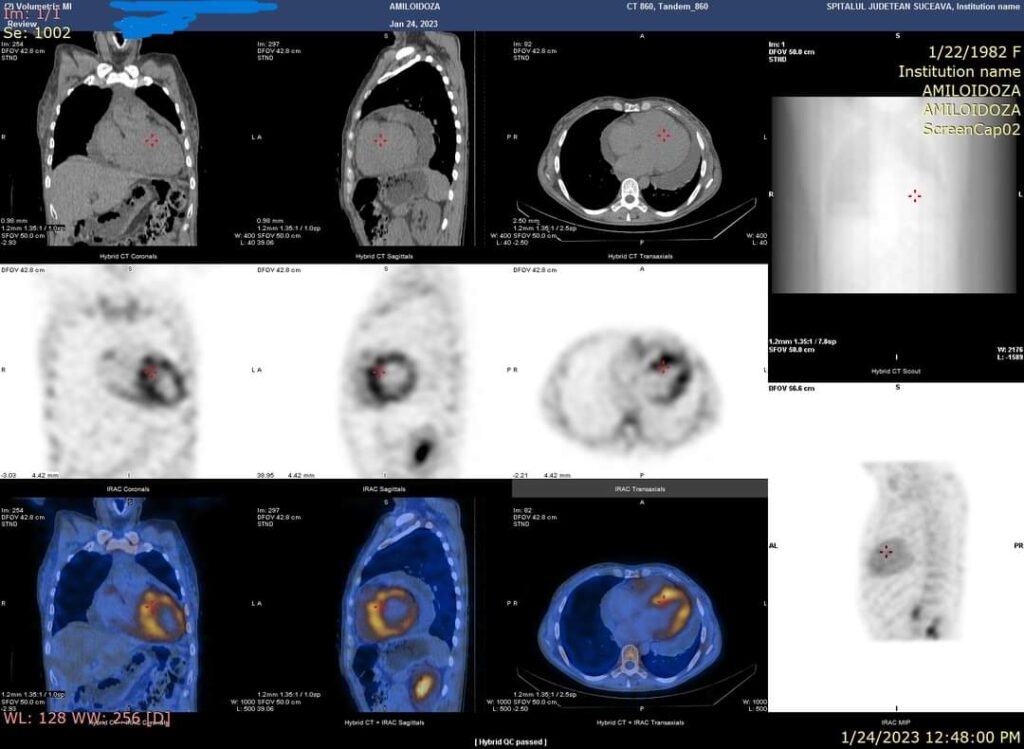

Recent, în Laboratorul de Medicină Nucleară al SJUSV în cadrul Centrului de diagnosticare și tratament al Amiloidozei coordonat de doctorul Daniela Neagu, medic primar neurolog, împreună cu doctorul Ramona Rusu, medic primar cardiolog, a fost investigat un caz de amiloidoză ereditară prin scintigrafie cu Tc99m-difosfonat. Fixarea radiofarmaceuticului în aria de proiecție cardiacă (scintigrafia corp întreg) similară fixării costale sau peste fixarea costală este diagnosticată pentru acest tip de patologie. Pentru reducerea rezultatelor scintigrafice fals pozitive, se poate efectua suplimentar achiziție SPECT/CT. Astfel se diferențiază dacă fixarea este la nivel miocardic, circulant sau extracardiac.